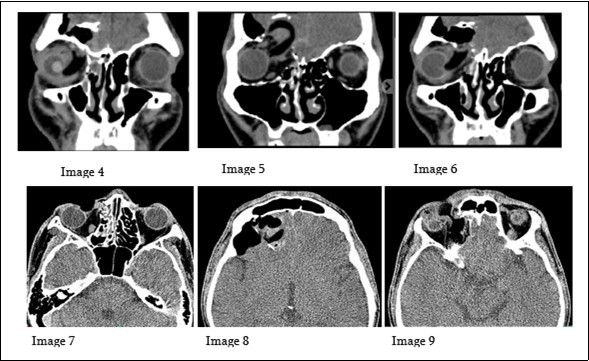

Patient underwent emergency cranial CT SCAN with orbital cuts to evaluate the extent of the injury. Figure 2.

Figure 2.The images (4-6) on the upper row, are serial coronal cuts of the cranial CT scan done for the patient. While images on the lower row (7-9) are axial cuts of the same scan.

There is a barrel shaped hypodense foreign body, seen to enter the anterior and medial aspects of the right orbit. The aforementioned foreign body is directed superiorly and is seen traversing or penetrating the right superior orbital wall, right medial lamina papyracea and the lateral and inferior border of the right frontal sinus, with its distal tip at the intracranial region at the right frontal lobe. There are fractured fragments, likely from the comminuted superior orbital wall and seen within the right frontal lobe. Along its track, it compresses the right globe and the right medial rectus muscle. Pneumocephalus in the right frontal convexity was noted and hemosinus in the right frontal and ethmoid sinus are likewise observed. Prolapse of the right medial orbital fat into the ipsilateral ethmoid sinus is noted.